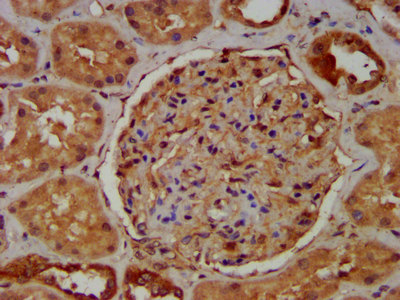

IHC image of CSB-PA863141LA01HU diluted at 1:400 and staining in paraffin-embedded human kidney tissue performed on a Leica BondTM system. After dewaxing and hydration, antigen retrieval was mediated by high pressure in a citrate buffer (pH 6.0). Section was blocked with 10% normal goat serum 30min at RT. Then primary antibody (1% BSA) was incubated at 4°C overnight. The primary is detected by a biotinylated secondary antibody and visualized using an HRP conjugated SP system.